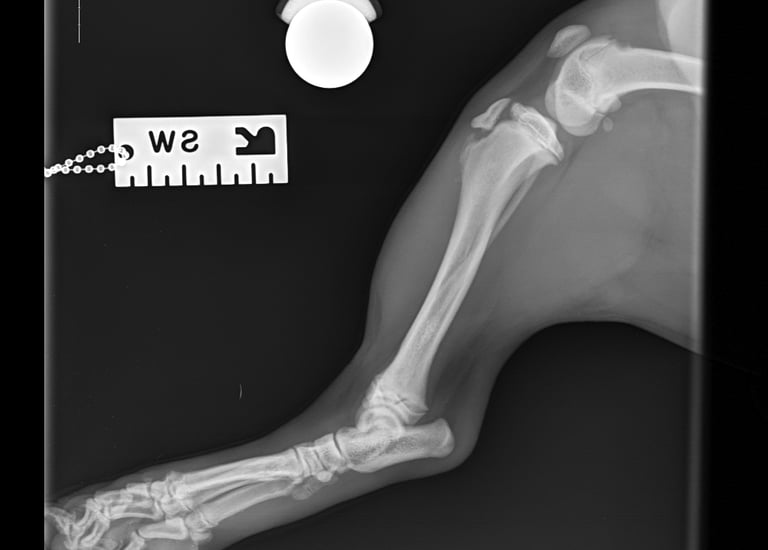

Lateral radiographs revealed a complete avulsion of the left tibial crest (Fig. 1), along with a mild lesion at the distal pole of the patella. For comparison, a lateral view of the right limb is included, demonstrating a normal appearance of the tibial crest growth plate (Fig. 2).

Fig. 2